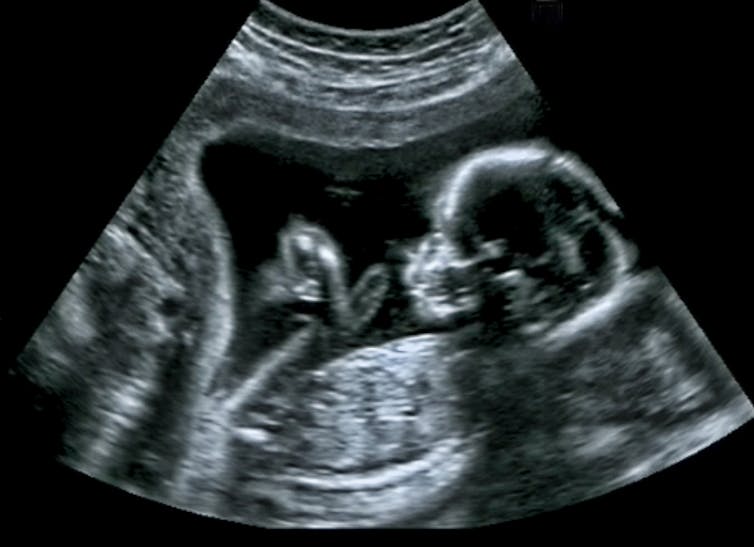

In the early 1960s, thousands of babies were born with malformed limbs as a result of their mother taking thalidomide – a drug used to treat morning sickness. The tragedy rocked the medical establishment and made doctors wonder what other drugs might have foetus-harming effects. Continue reading